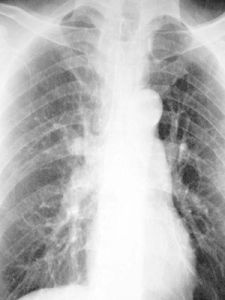

心臟各房室增大時,心臟形狀亦發生改變,在後前胸片上呈三種心型。1.二尖瓣型常見於二尖瓣病變、慢性肺原性心臟病、心間隔缺損、肺動脈狹窄等,表現為右心緣膨隆,左心緣下段圓鈍,心腰豐滿或弧形突出,主動脈結小,心影呈梨形。

2.主動脈型常見於高血壓和主動脈瓣病變,表現為左心尖向左下延伸,心腰凹陷,主動脈結突出,心影呈靴型。

3.普大型常見於心肌炎、全心衰竭、心包積液等。表現為心影向兩側增大,較對稱。

心臟各房室增大時,心臟形狀亦發生改變,在後前位胸片上呈三種心型。1.普大型

表現為心影向兩側增大,較對稱。常見於心肌炎、全心衰竭、心包積液等。

2.主動脈型

表現為左心尖向左下延伸,心腰凹陷,主動脈結突出,心影呈靴型,常見於高血壓和主動脈瓣病變。

3.二尖瓣型

表現為右心緣膨隆,左心緣下段圓鈍,心腰豐滿或弧形突出,主動脈結小,心影呈梨形,常見於二尖瓣病變、慢性肺源性心臟病、心間隔缺損、肺動脈狹窄等。

X線檢查,心臟擴大包括心壁肥厚和心腔擴大,兩者常並存。是心臟病的重要徵象。治療原則